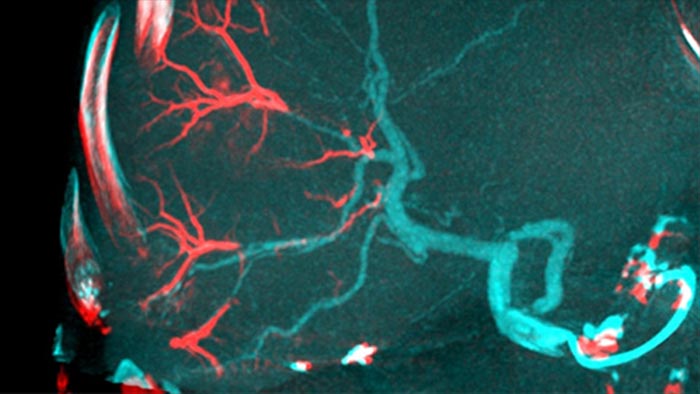

Функция CBCT Dual обеспечивает получение данных артериальной фазы в режиме 3D для визуализации сосудистых структур и данных постартериальной (отсроченной) фазы для визуализации накопления контрастного вещества посредством одного автоматического шага5.

Функция Dual View позволяет одновременно просматривать два набора данных КТ-подобных изображений. Артериальная и отсроченная фазы могут отображаться рядом друг с другом или в виде объединенного наложения.

Функция Dual View обеспечивает одновременную визуализацию 3D-изображения артериальной фазы до эмболизации и изображения после эмболизации для наглядной оценки результата процедуры.